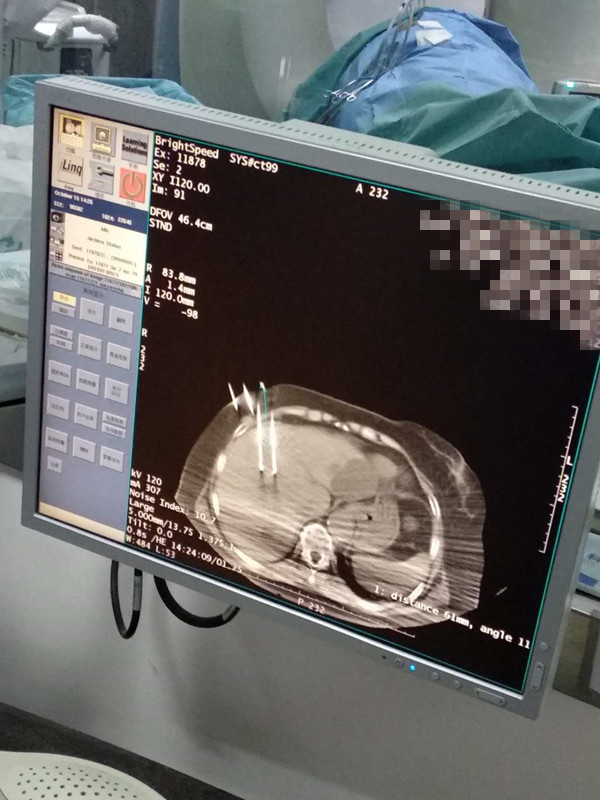

73岁患者肝部氩氦刀冷冻消融

发布人:美国氩氦刀技术官方网站    发布时间:2020/10/16 16:15:21